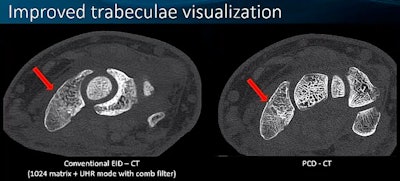

She then "unpacked" some of these benefits, noting that PCCT not only produces images of thick body regions with less streaks and blurring and clearer images in patients with metal artifacts such as spine hardware compared to conventional CT. It also allows clinicians to see smaller things (for example, the anterior choroidal artery), improves visualization of the trabeculae, and detects small calcifications that conventional CT misses.